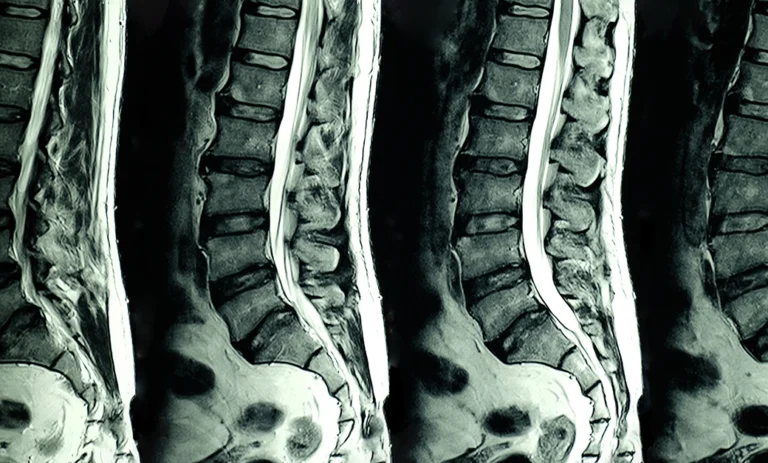

12 Exercises To Avoid According to an Anchorage Chiropractor When You Have Sciatica

Are you suffering from sciatica pain and wondering if exercise can help? They can, but there are some exercises that you should avoid. Your Anchorage chiropractor is well-versed in the subject. First, avoid any exercise that causes you pain. After that, it is generally best to avoid exercises that stress